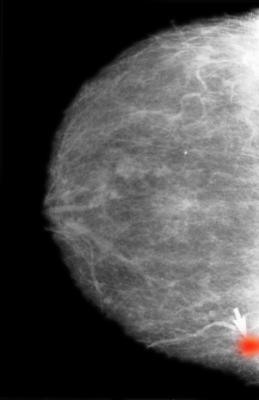

August 2, 2023 — Mammography screening supported by artificial intelligence (AI) is a safe alternative to today’s conventional double reading by radiologists and can reduce heavy workloads for doctors. This has now been shown in an interim analysis of a prospective, randomized controlled trial, which addressed the clinical safety of using AI in mammography screening. The trial, led by researchers from Lund University in Sweden, has been published in The Lancet Oncology.

“In our trial, we used AI to identify screening examinations with a high risk of breast cancer, which underwent double reading by radiologists. The remaining examinations were classified as low risk and were read only by one radiologist. In the screen reading, radiologists used AI as detection support, in which it highlighted suspicious findings on the images”, says Kristina Lång, researcher and associate professor in diagnostic radiology at Lund University and consultant at Skåne University Hospital, who led the study.